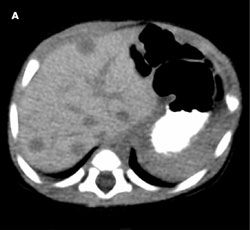

A complete blood cell count with differential, and electrolyte and liver enzyme levels are normal. CT scans of the abdomen without (A) and with (B) contrast show multiple solid hypoattenuated lesions in both lobes; the largest lesion (arrow), of 11 mm, in hepatic segment VI significantly enhances with intravenous contrast.